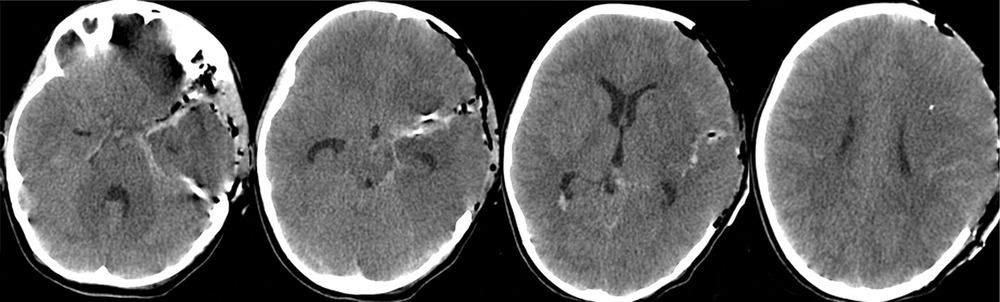

После экстренно проведенной коррекции ВЧГ (седация пропофолом, гиперосмолярная терапия, гипервентиляция) наблюдалась положительная динамика неврологической симптоматики в виде сужения зрачков и появления фотореакции с обеих сторон. В дальнейшем параметры искусственной вентиляции легких (ИВЛ) были подобраны так, чтобы обеспечить нормовентиляцию: PaCO2 в переделах 35—45 мм рт. ст. и PaO2 в пределах 100—110 мм рт. ст. Был начат инвазивный мониторинг артериального давления (АД), при этом системное АД без вазопрессорной поддержки составляло 100/60—110/70 мм рт.ст., ЧСС — 77—90 уд/мин. В связи с клинико-рентгенологической картиной отека мозга и дислокацией срединных структур мозга, согласно КТ, коматозным состоянием пациентки и наличием реакции на экстренные терапевтические манипуляции было принято решение об экстренном выполнении нейрохирургической операции. В течение полутора часов после поступления ребенка было выполнено нейрохирургическое вмешательство: клипирование аневризмы бифуркации левой СМА, удаление внутримозговой гематомы левой височной доли, наружная декомпрессия черепа слева. Операция была завершена установкой паренхиматозного датчика фирмы Codman в левую премоторную область для мониторинга внутричерепного давления (ВЧД) и контроля церебрального перфузионного давления (ЦПД). ВЧД при установке датчика составило 2 мм рт.ст. На следующий день после операции выполнена контрольная КТ головного мозга, по данным которой диффузный отек сохранялся (рис. 2).